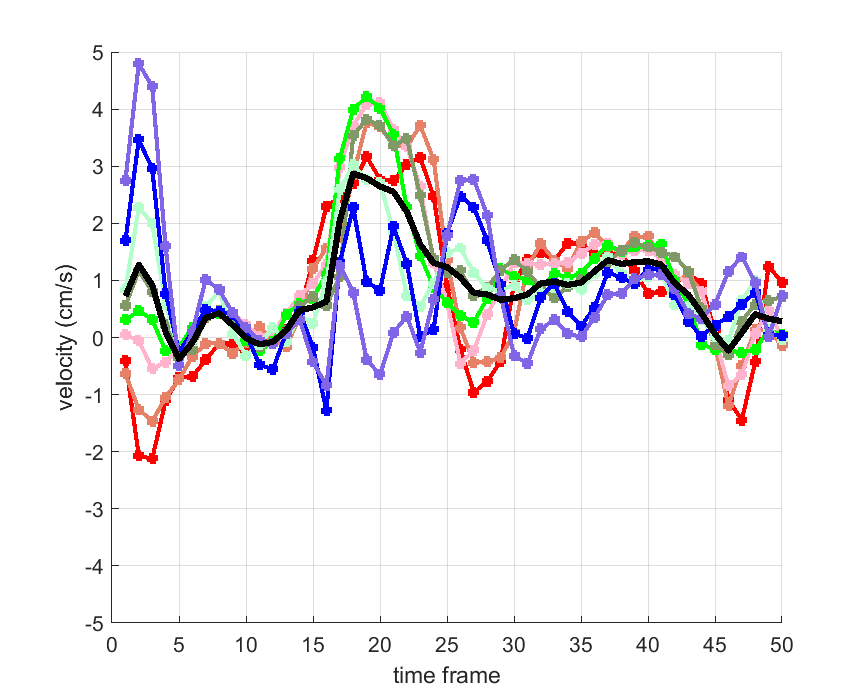

Time courses of the estimated translational component per subject, frame, slice and volume along the 3 velocity directions x, y and z are presented in Fig.6 - Fig.8.